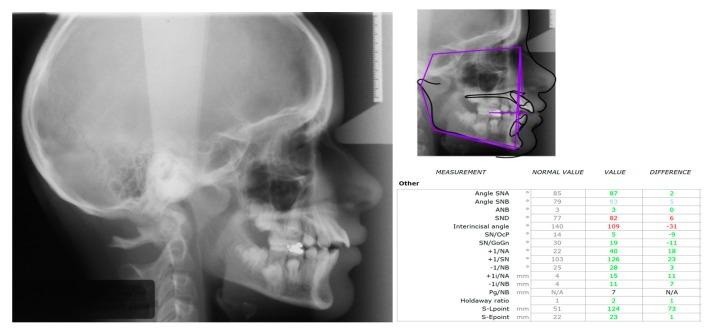

The purpose of this paper is to present a case of an impacted mandibular first molar associated with a dentigerous cyst and a missing mandibular second molar in an 11-year-old girl that was treated with combined surgical and orthodontic procedures. After clinical and radiographic evaluation, marsupialization of the cyst was decided, and a molar attachment was bonded on the buccal side of the impacted molar as a part of a full orthodontic treatment with fixed appliances. After 18 months of orthodontic traction, the molar was moved to a more advantageous position, and new bone apposition was observed on the site of the cystic lesion. Histological examination confirmed a dentigerous cyst. The molar was left to erupt spontaneously for 14 more months. A functional occlusion was finally achieved. An interdisciplinary approach proved to be an effective modality in treating a large dentigerous cyst associated with a deeply impacted first mandibular molar, presenting many advantages, such as new bone apposition and patient comfort.

本文旨在介绍一例11岁女孩的病例,该患者下颌第一磨牙阻生并伴有含牙囊肿,同时下颌第二磨牙缺失,采用手术和正畸联合治疗。经过临床和影像学评估后,决定对囊肿进行袋形术,并在阻生磨牙的颊侧粘结磨牙附件,作为固定矫治器全口正畸治疗的一部分。经过18个月的正畸牵引,磨牙移动到更有利的位置,并且在囊性病变部位观察到新骨形成。组织学检查证实为含牙囊肿。磨牙又自行萌出了14个月。最终实现了功能性咬合。跨学科方法被证明是治疗与下颌第一磨牙深度阻生相关的大型含牙囊肿的有效方式,具有许多优点,如新骨形成和患者舒适度高。